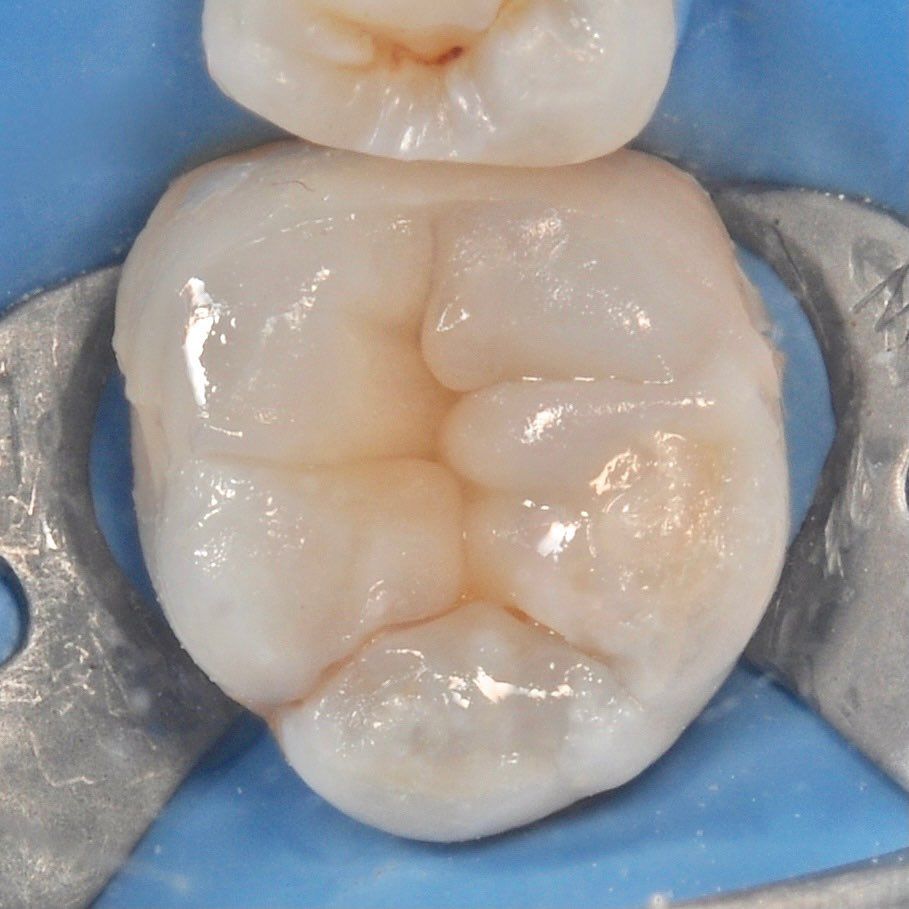

зуб с обработанными каналами

Лечения пульпита

Каналы наших зубов можно представить как дерево имеющее множество ответвлений. Задача врача провести их обработку сохранив ткани зуба.